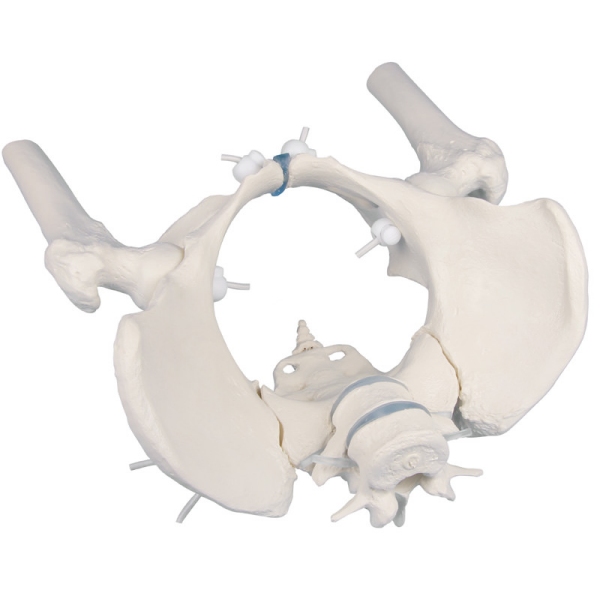

Ženska medenica s križnico, dvema ledvenima vretencema in stegnenico, gibljiva

Naravni odlitek medenice odrasle ženske Medenico je mogoče hitro in enostavno razstaviti. V celoti je pritrjena z gumijastimi trakovi, ki omogočajo izjemno gibanje. S fleksibilno pritrjenima L5 in L4. Stegnenični peclji so premični in odstranljivi.